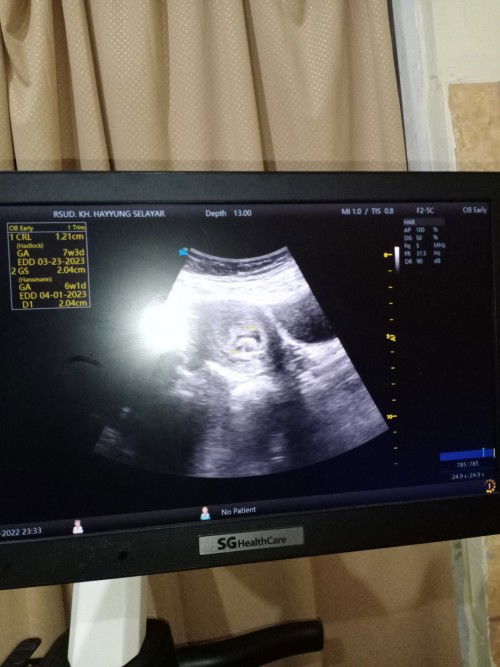

Berdasarkan hpht 30 mei, harusnya usia kehamilan ku sudah 9 mg 3 hr. Tapi pas usg malah jadi 5 mg 5 hr, trus keluar flek coklat. Dan hasil USG masih keliatan kantong. Terus didiagnosa abortus imminens. Disuruh bedrest total aja bund. Tapi aku takutnya hamil kosong bun. Ada yg pernah punya pengalaman yg sama bun?#seriusnanya #bantusharing

Hari ini saya pergi usg bund, soalnya ada flek coklat. Usia kehamilan berdasarkan hpht harusnya sudah 9 mg, tapi pas usg jadi 5w4d dan masih kantong yg keliatan. Jadi didiagnosa abortus imminens. Adakah yg punya gejala sama bun? Gimana cara mengatasinya bun?#seriusnanya #bantusharing #ingintahu #firstmom #pleasehelp #firstbaby